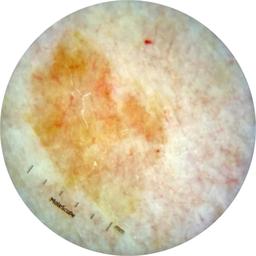

ISIC_7193897

1979 x 1979

Clinical

Field Value

acquisition_day 251

age_approx 65

anatom_site_1 Lower extremity

anatom_site_general lower extremity

concomitant_biopsy False

diagnosis_1 Benign

diagnosis_confirm_type single image expert consensus

family_hx_mm False

image_manipulation instrument only

image_type dermoscopic

lesion_id IL_3780211

patient_id IP_3751325

personal_hx_mm True

sex female